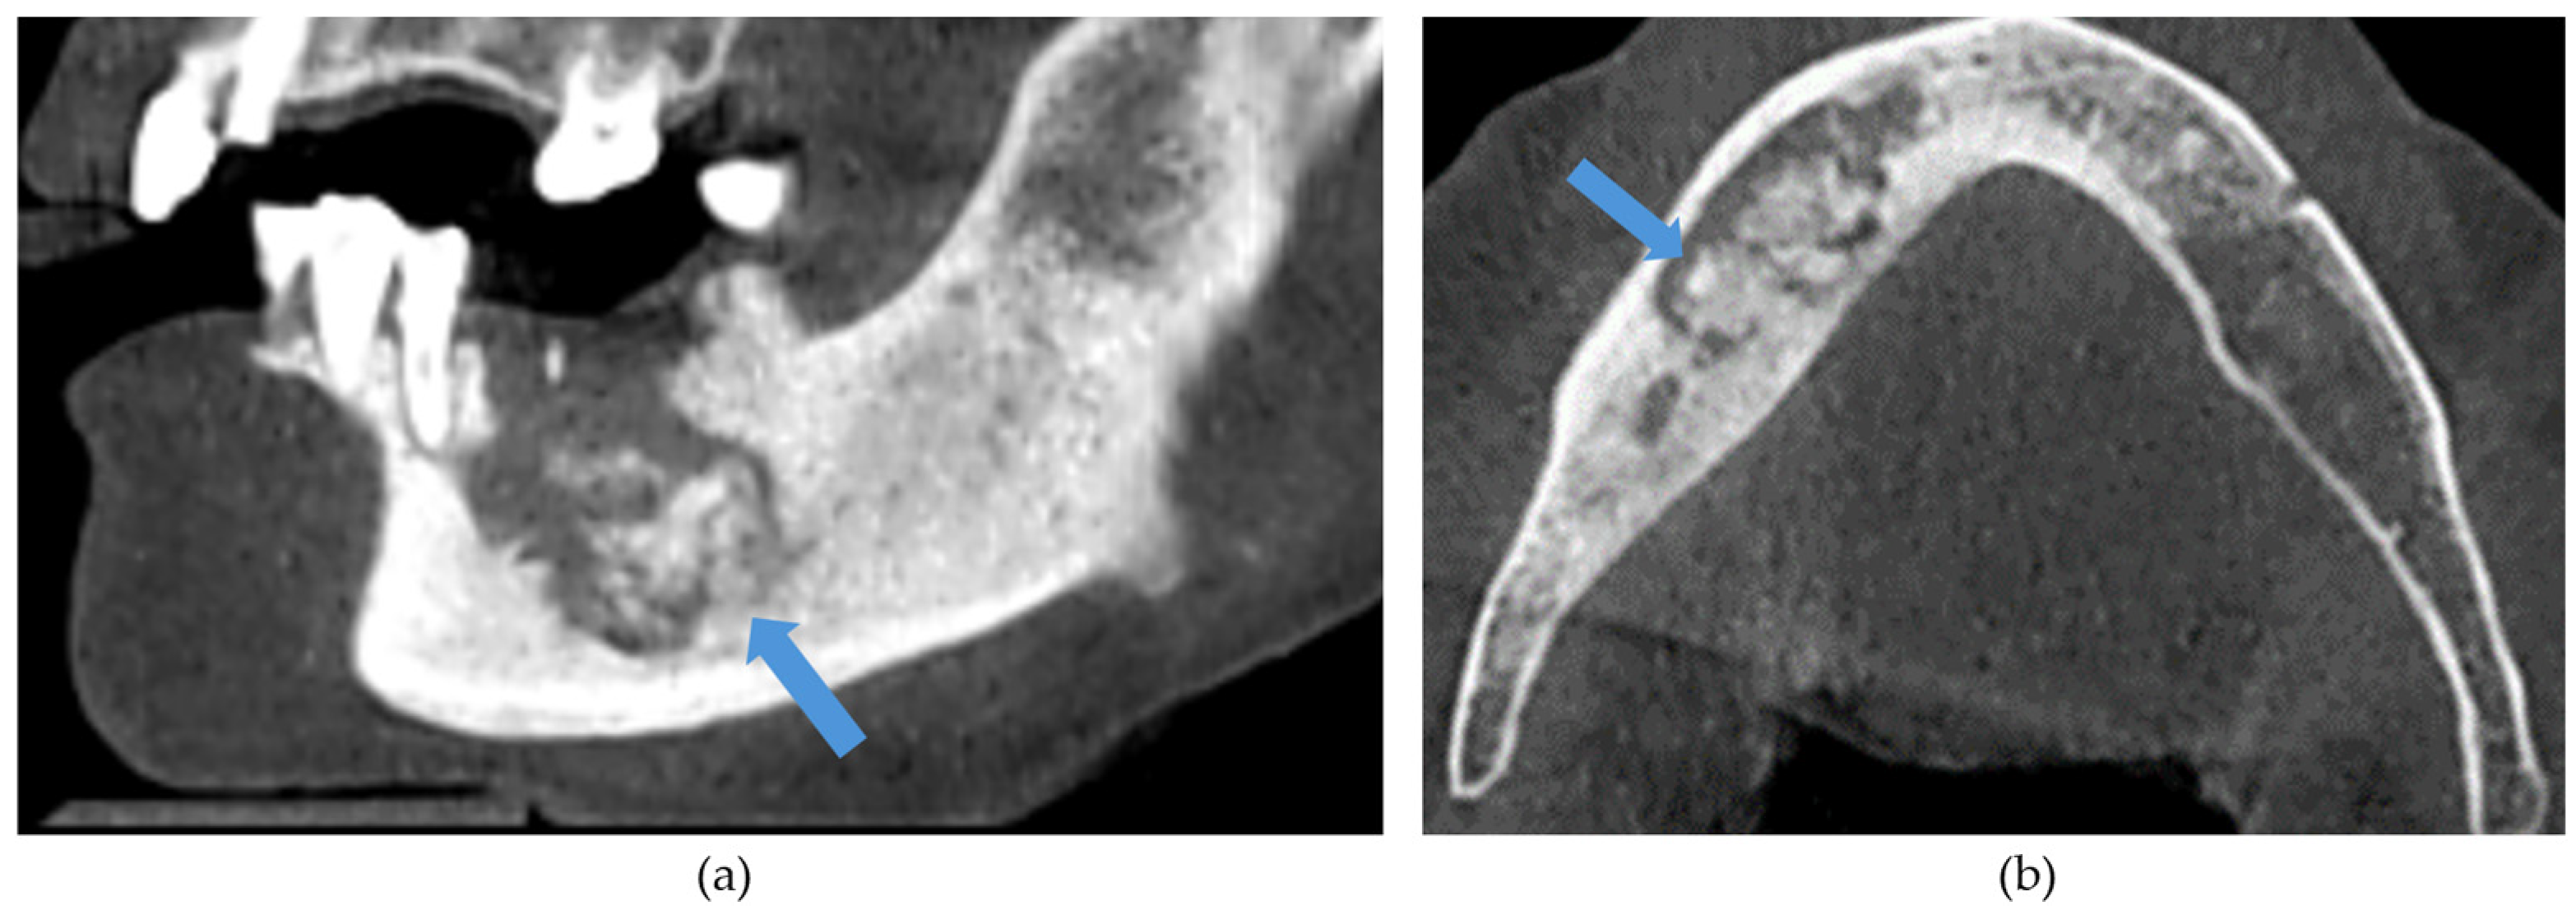

The CBCT findings commonly observed in patients with MRONJ are osteosclerosis, osteolysis, periosteal reaction, and sequestration [13,14,15,16,17,18]. The histomorphological analyses of MRONJ lesions have revealed three distinct patterns: (1) prominent bone resorption in regions of active inflammation, (2) acellular necrotic sequestra with large Haversian canals, and (3) increased inter-osteonic bone deposition with smaller Haversian canals and trabecular thicknesses in non-necrotic regions [19]. Abnormal bone remodellling characterised by reduced osteoclastic activity and increased appositional osteogenesis contributes to the radiological pattern observed in MRONJ lesions. In earlier stages of MRONJ, non-healing extraction sockets, the thickening of lamina dura, and periodontal ligament (PDL) space widening may also be observed [14,16,18,20]. In maxillary MRONJ, more prominent maxillary sinus mucosal thickening can be observed, although no significant differences in sinus volumes have been noted [21]. These radiological manifestations are illustrated in Figure 1, Figure 2, Figure 3, Figure 4 and Figure 5.

Figure 2. (a) Sagittal and (b) axial sections demonstrating generalized osteosclerosis of the mandible. Arrow demonstrates mild mental foramen narrowing.